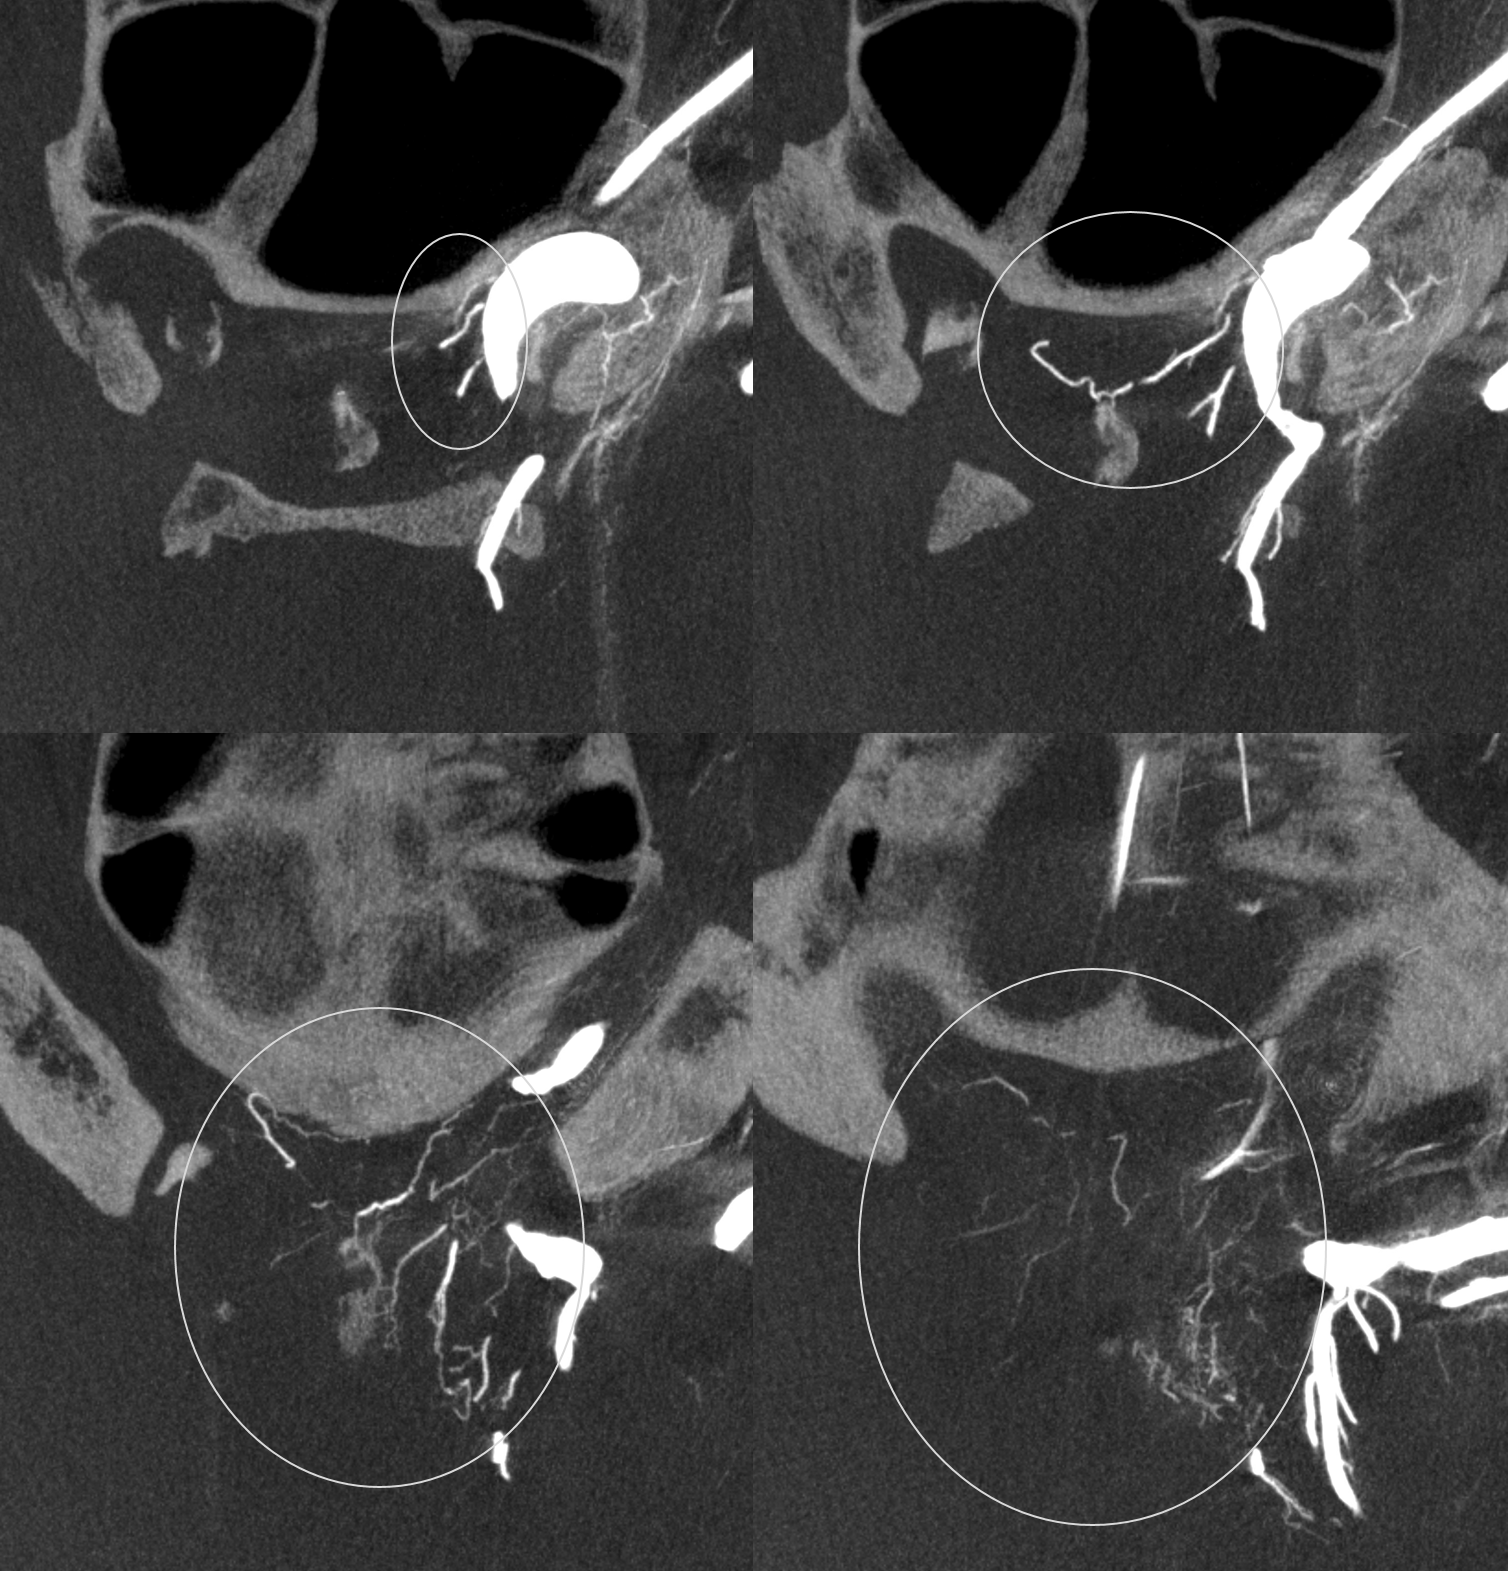

Stereos and MIPs. Both superior and inferior hypophyseals are well seen. The superior hypophyseal, despite being invisible on standard issue views, is quite large, even having two branches to the hypophysis.

Case courtesy Dr. Eytan Raz — here is a beautiful example of a very dominant superior hypophyseal artery (arrow) supplying the posterior hypophysis (arrowhead), with a correspondingly small inferior hypophyseal contribution from the MHT (dashed arrow)

Cross eye stereo

View from the back — again small inferior hypophyseal, big superior hypophyseal — balance again… See the beautiful vascular ring of the posterior pituitary — the connecting it with the contralateral side

Cross-eye stereo

MIP image shows the sella nicely — and helps prove its posterior pituitary

Pure arrowless images — easier to steal…

Of course, there is an aneurysm here — the branch point camp would point out how this larger than usual branch is a setup for aneurysmal formation. Naturally…